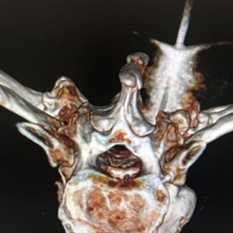

Злокачественную опухоль позвоночника и костей черепа зачастую сложно удалить, потому что рядом находятся жизненно важные структуры. В таких случаях прибегают к специальным хирургическим методам:

- Выскабливание пораженного участка кости.

- Криохирургия - уничтожение опухолевых клеток низкой температурой с помощью жидкого азота.

- Костный цемент на основе полиметилметакрилата помогает закрыть отверстие, которое осталось после выскабливания и криохирургии, кроме того, при застывании он выделяет тепло, которое уничтожает опухолевые клетки.